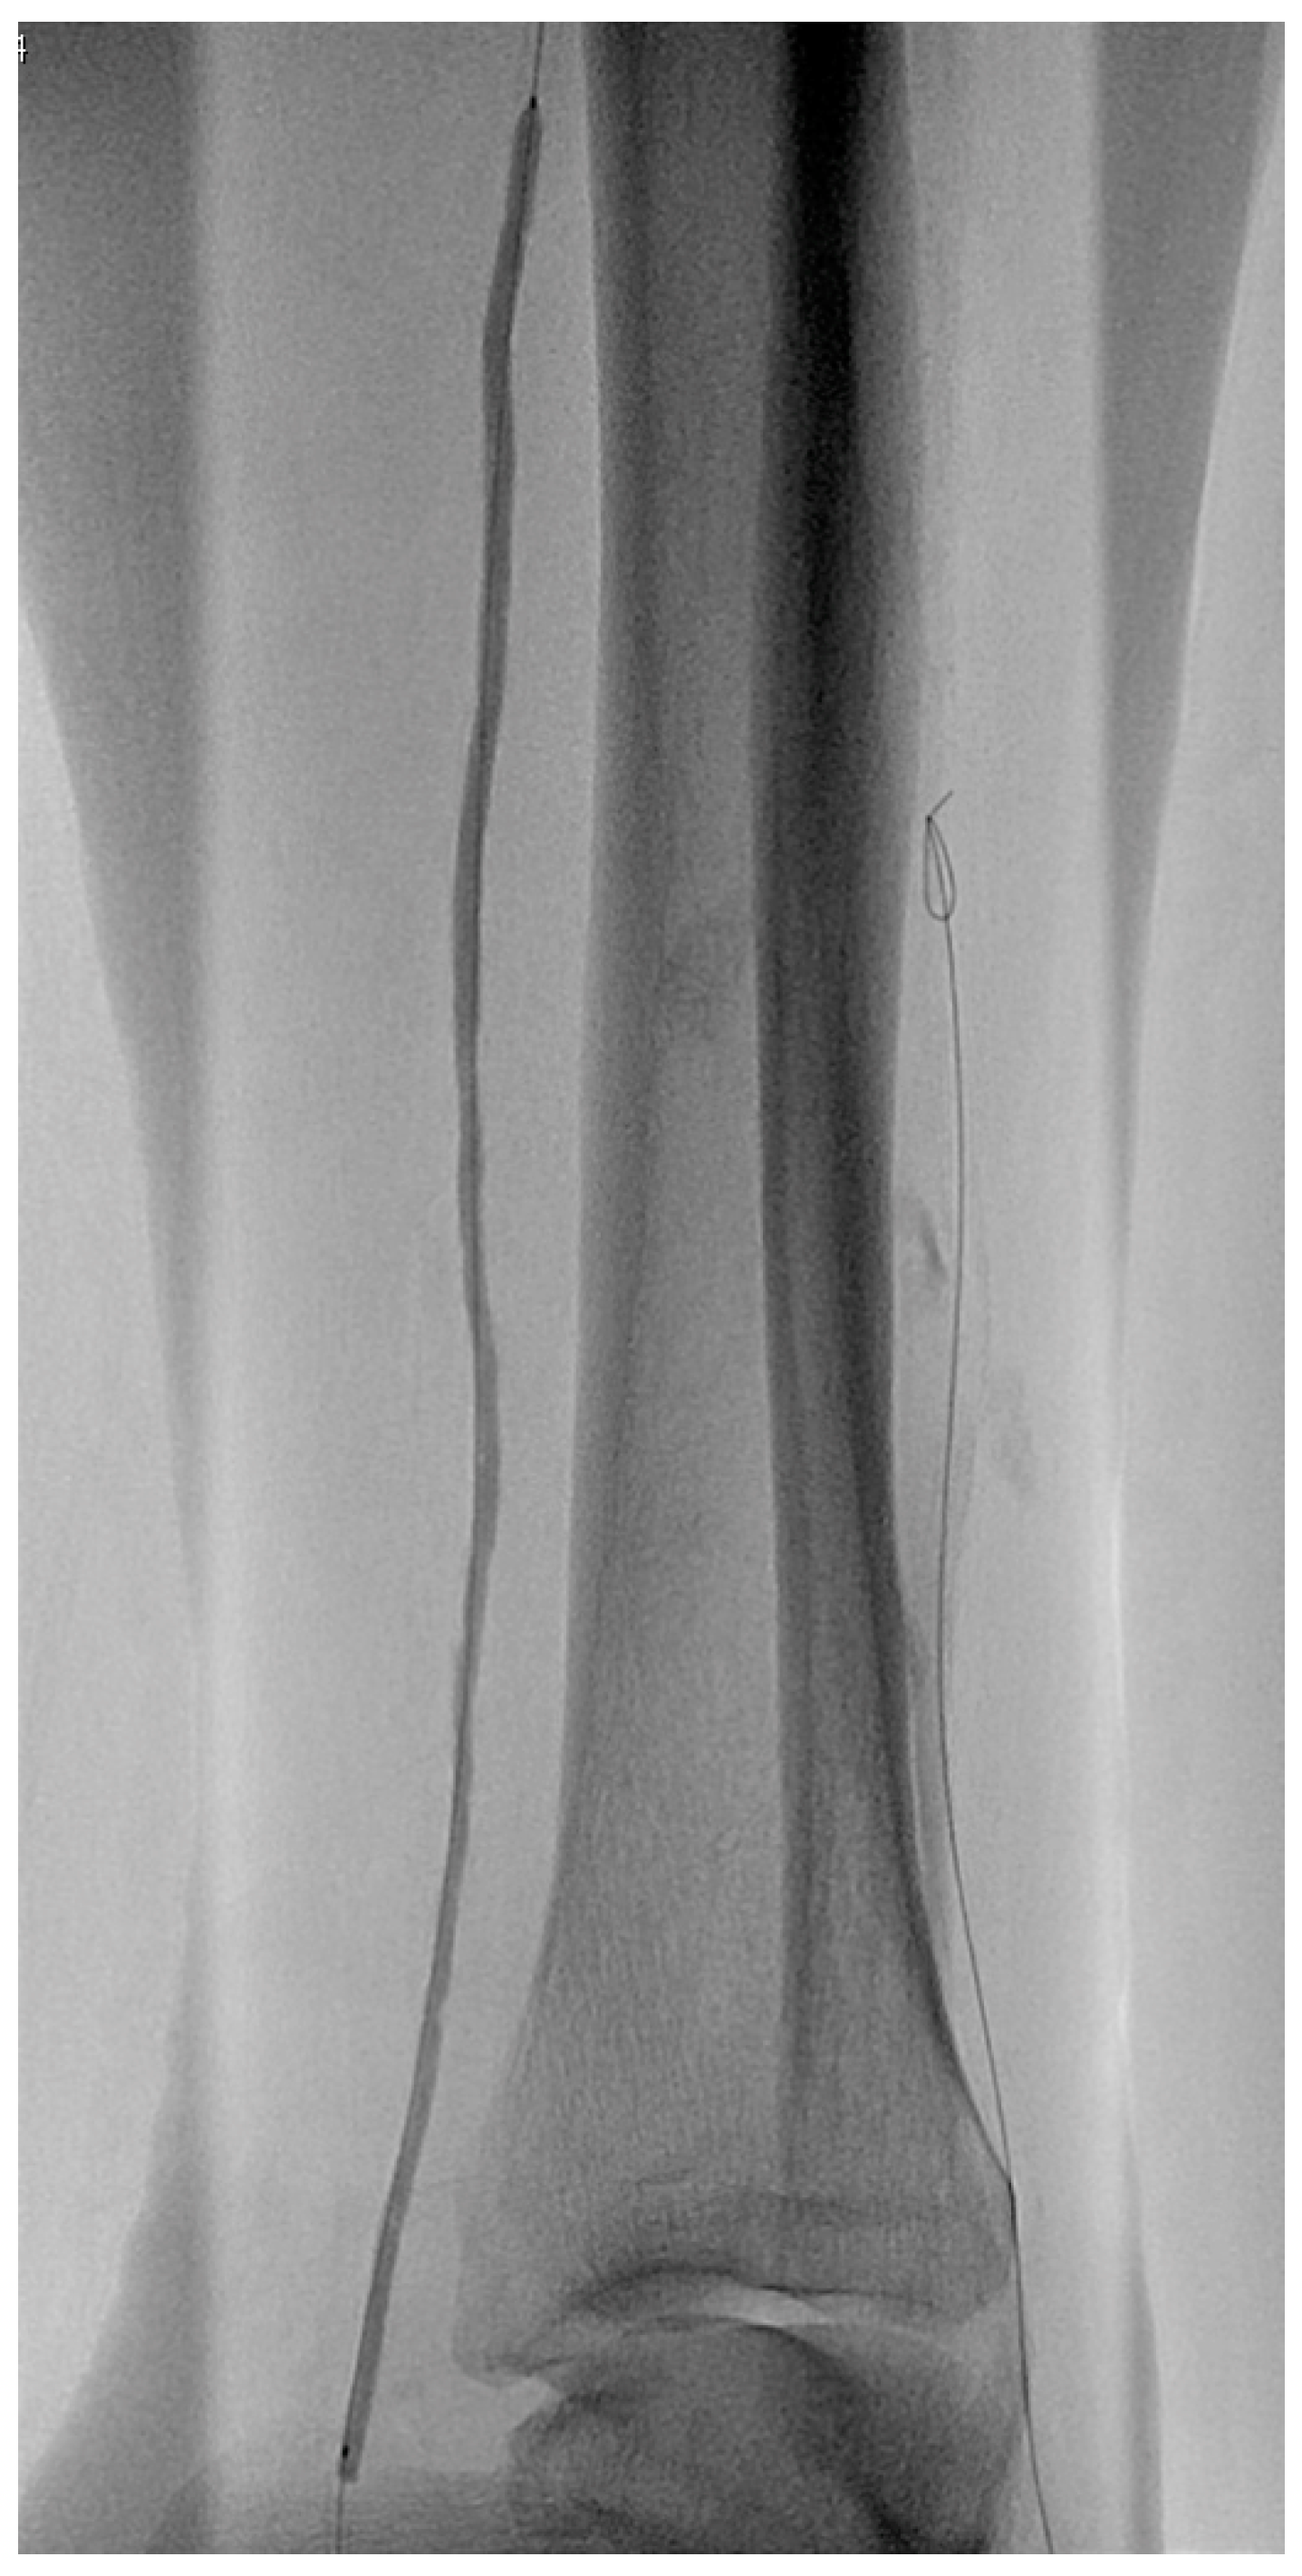

2.4. Imaging

3.3. Anatomic Pattern of Disease